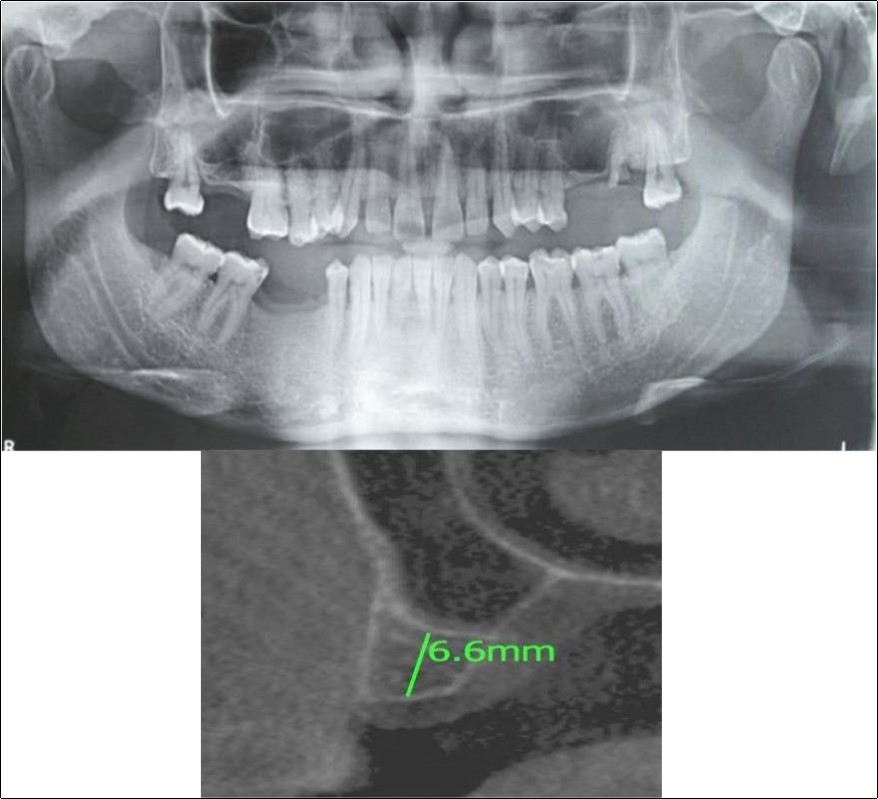

Figure 11.(a,b) Pre-treatment OPG and cross section of CBCT showing residual alveolar bone height for Case No.3

Figure 12.(a,b) Post-treatment OPG and cross section of CBCT showing residual alveolar bone height for Case No.3;

Clinical and Radiological Assessment:

1.Partially edentulous maxillary and mandibular arches with missing 17, 26, 45, 46;

2.Increased pneumatisation of right maxillary sinus;

3.Height of available bone- 6.6mm;

4.Transverse thickness of available bone (CBCT evaluation)- 11mm;

5.Inter-ridge space adequate to place implant (10mm).